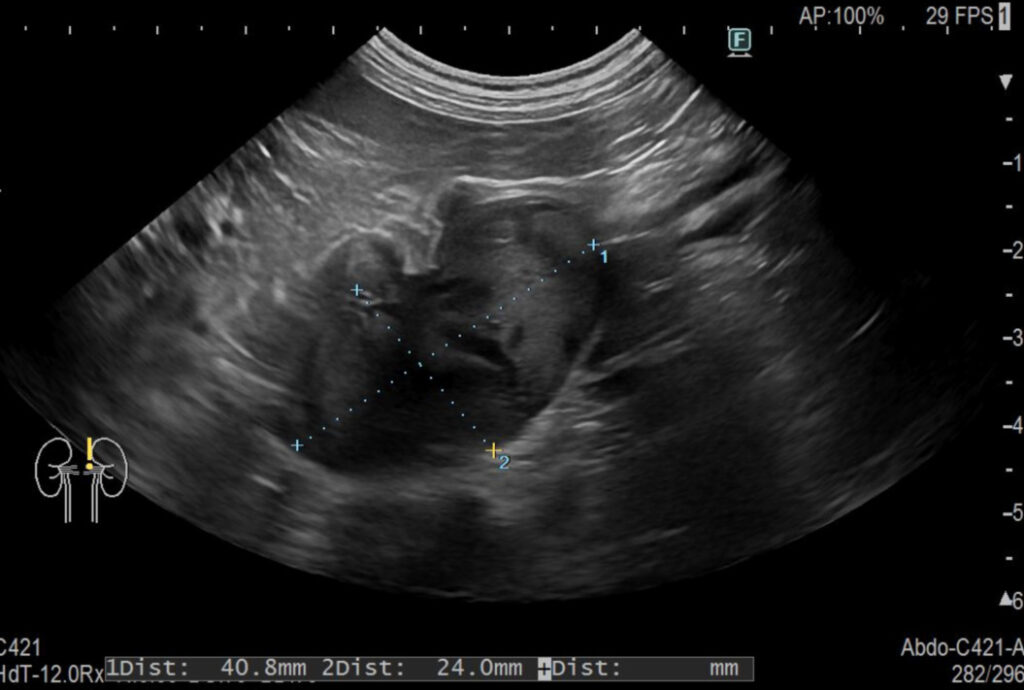

X線検査、超音波検査、細胞診検査で明らかな遠隔転移は認められなかったため、腫瘍の摘出とステージングのための領域リンパ節切除を実施しました。サージカルマージンは水平で1.5cm、底部で筋膜1枚としました(図)。